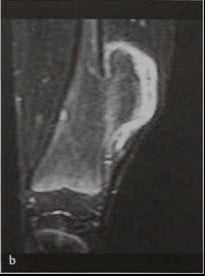

Остеохондрома (костно-хрящевой экзостоз бедренной кости ) Девочка 12 лет, визуализация дистальной части диафиза кости пораженного экзостозом. МРТ. Интенсивность сигнала сходна с жировой тканью на Т1-взвешенной последовательности (а).

Хрящевой колпачок, имеющий выраженную гиперинтенсивность, выявляется на изображении последовательности STIR с подавлением МР-сигнала от жировой ткани (b), и имеет наибольшую толщину 1,5 см. Экзостоз удален. Злокачественный процесс не обнаружен.